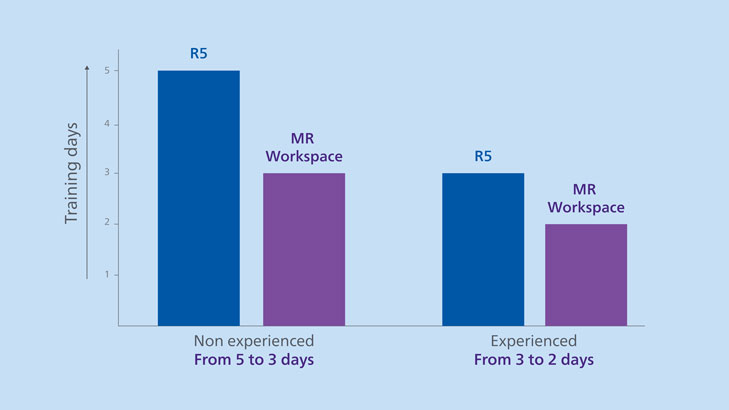

Imaging professionals ramp up quickly with MR Workspace. In a study, Daniel Fino Villamil and his team of biomedical engineers compared training differences between the previous Ingenia user interface and MR Workspace. The study involved 20 individuals from the MRI service, 10 of whom were inexperienced or experienced MR technologists. The researchers found that it took fewer days to train both experienced and inexperienced technologists on Release 10 versus Release 5.

Switching from the previous MR user interface to MR Workspace reduced training times from 5 days to 3 days (-40%) for inexperienced technologists and from 3 days to 2 days (- 33%) for experienced technologists.